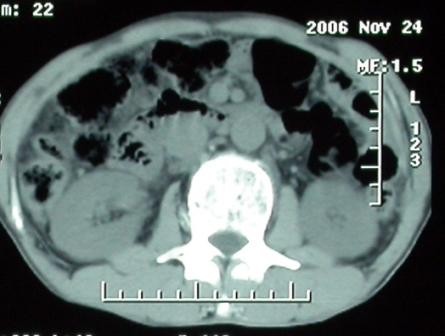

影像表现:胆囊扩张、肝内胆管不扩张,且见肝脏内树枝样气体影;十二指肠后方等密度占位,中心有不规则囊变区。增强实质部分轻度强化。下部腔静脉未强化------有栓子吗?

1、胰头部占位:胰管轻度扩张(可疑双管征),主要考虑恶性肿瘤,胰头癌?十二指肠间质瘤?后腹膜肿瘤?

2、门静脉高压症,主要考虑胰头部肿块压迫或者浸润所致肝前性门静脉主干受压;肝功能尚可,脾脏不大,无脾亢;

3、胆囊积液、肝胆管积气、胆道扩张伴有胆道感染;

4、右肝后上段占位(考虑肝胆管结石伴肝组织萎缩?)

5、下腔静脉受压;

6、左半肝缺失,原因不明?

补充一点重要资料:今日查afp大于正常值10倍以上。因此,本病例最大可能应该是肝癌。

手术结果:

肝脏尾状叶肝癌(沿肝十二指肠韧带向下韧带内生长,门腔间隙外压增大),大结节性肝硬化,胆囊积脓,胆道感染。术中见肝外胆道2cm直径,肿瘤向前压迫胆管至扁平状态。